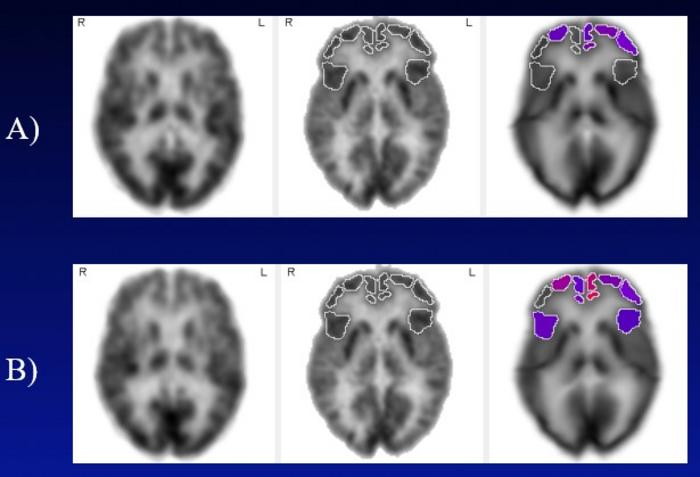

From the Alzheimer’s Disease Neuroimaging Initiative database, researchers identified subjects with amnestic mild cognitive impairment who were screened for hearing impairments and had annual FDG PET brain scans archived at, and for years after, baseline. These subjects were subsequently categorized into groups with untreated hearing loss, those with treated hearing loss by hearing aids, and a demographically matched control group with no diagnosed hearing impairment. Brain metabolism in 47 standardized volumes of interest from each of the FDG-PET scans was quantified and compared within- and between-groups in rate-of-change analyses.

The hearing loss group demonstrated significant annual metabolic decline in six frontal cortical regions and two superior temporal regions, while the control group exhibited significant decline only in two superior temporal regions, likely reflective of presence of an early neurodegenerative process in these subjects with mild impairment, but in none of the frontal cortical regions.

Strikingly, the hearing aid group did not experience significant annual metabolic decline in any frontal cortical region. Furthermore, direct statistical comparison of rates of decline in difference-of-differences analyses demonstrated that multiple frontal cortical regions declined significantly faster in the untreated hearing loss group than in the group treated with hearing aids, and that no frontal cortical region declined significantly faster in the hearing aid group than in the control group.